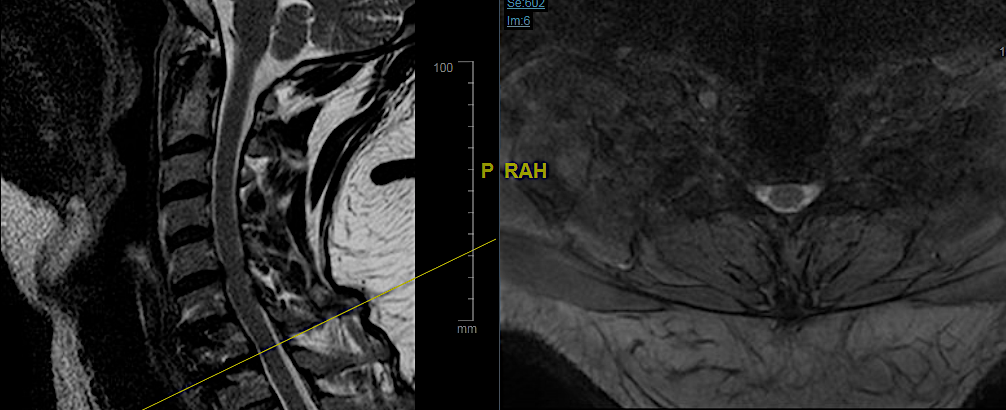

T2 6 meses

STIR 6 meses

La evolución de la paciente fue favorable, sin presentar complicaciones torácicas ni síndrome de Horner. El objetivo de la cirugía fue descomprimir la raíz C8 en primer lugar y aliviar la clínica; en segundo lugar, lograr una descompresión de canal para evitar la aparición de mielopatía. Para retirar el engrosamiento de LVCP (que considero que no ejercía una compresión medular significativa, hubiese sido necesario un abordaje más agresivo (esternotomía + corpectomía Th2) que hubiesen incrementado los riesgos de complicaciones.

En caso de que ese engrosamiento progrese y pueda dar clínica, me plantearía un abordaje posterior con artrodesis y resección de arco(s) posterior(es). De momento, la paciente sigue controles evolutivos anuales.